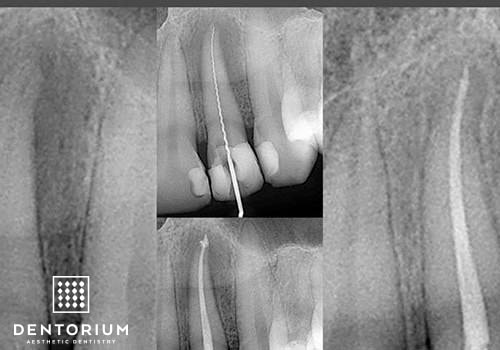

Endodonzia - Cura canalare

La sanazione della radice dentale e' necessaria quando c'e' l'infiammazione del nervo (infiammazione acuta) oppure con...